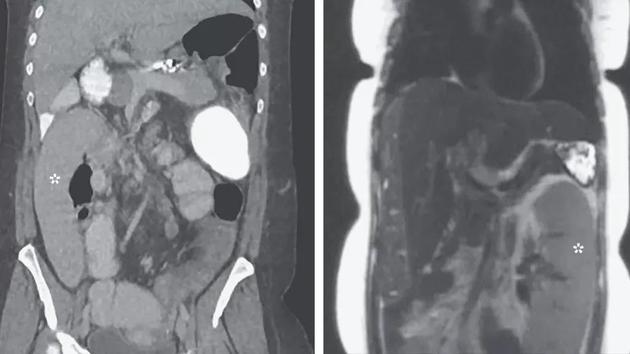

"游走脾"是一种十分罕见的情况,通常是由于固定该器官的韧带松弛导致,当它在体内游走时,会挤压其他的器官,最常见的症状是腹痛。当女性被紧急送医时,医生发现了她的脾移动了30厘米,直接从胃部上方(左上)移到了右侧的下方。而她的脾之所以有异常举动,还得从她的肝说起。

她的肝脏出现了原发性硬化性胆管炎,无法有效地将消化液从肝脏输送到小肠。这种症状会导致肝脏硬化,影响血液流动。而这些血液只好回流到脾脏。而脾脏被涨大时,其连接的韧带就会变松,最后的症状就是脾脏脱离原来的位置,开始游走。当然,这个异常的脾脏最后的结局都不太好,研究人员表示,如果放任不管,它会导致其周围的血管纠缠,最后坏死,而为了救患者,最有效的措施摘掉脾脏了。